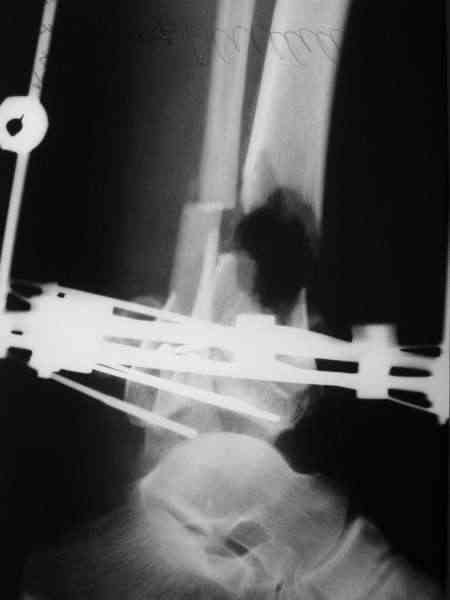

НЗ> на снимке результат сразу после операции и устранения "холостого

НЗ> хода". Ведется постепенная дистракция. Этапных снимков не

НЗ> проводил, т.к. по отломкам в ране можно ориентироваться в степени

Надо сначала убрать мертвые куски кости, которые видно на фото, потом истинный размер дефекта обозначится. После этого, возможно, получится сделать vessel loop для постепенного сведения краев. Или пойти на укорочение с гофрированием, в общем, вариант закрытия пока рано обсуждать.

НЗ> Что сделано не так (требуется ли перекомпоновка АВФ для более

Да тут пока не до репозиции. Интересно, голеностопный сустав удастся ли сохранить. Как гнойный процесс купируется, наверно, есть смысл фиксировать дистальный эпиметафиз в отдельной опоре, потом стопу пораньше освободить.